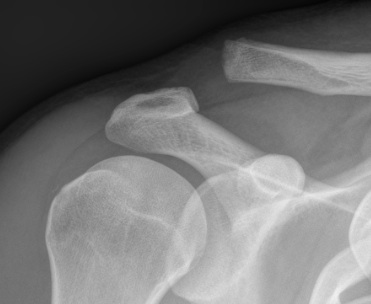

Allman grades I-III 1967 / Rockwood modified 1989 Classification

I AC ligament sprained, but CC ligaments intact (xray normal)

II AC ligament disrupted, CC ligaments sprained but intact (displaced < 100% CC distance)

III AC & CC ligaments ruptured (displaced up to 100% of CC distance)

IV AC and CC ligaments disrupted and clavicle displaced posteriorly into trapezius

V High dislocation (100 - 300% CC distance) - disrupted trapezius & deltoid and end of clavicle subcutaneous

VI Subcoracoid dislocation

X-rays

Zanca view

- specific for AC joint

- 10o cephalad, 50% underpowered

Stress views

- hold weights in each arm